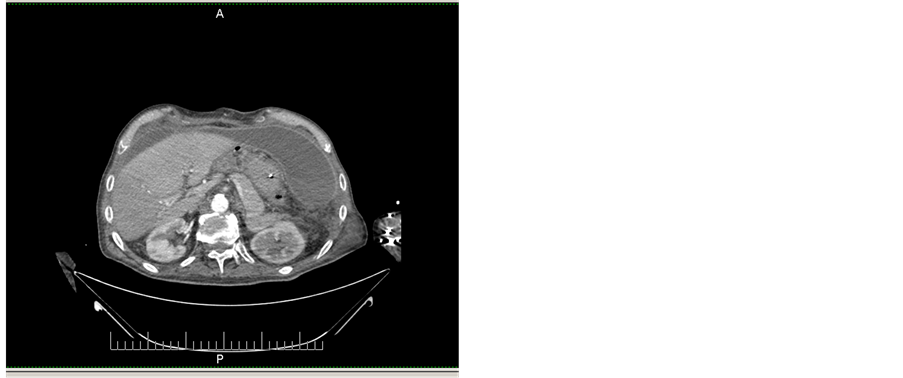

The patient returned to our ward in the 28th POD, breathing spontaneously, with normal diuresis but still febrile. Within a few hours since the admission an abundant, purulent like discharge started to flow from the colostomy edges with characters very similar to enteric fluid. A new CT scan revealed two large purulent communicating collections in the right and left paracolic gutters (Figure 6): in spite of percutaneous CT guided drainage, pus evacuation was not satisfactory. Such condition, together with the suspicion of an enteric leakage brought to a new laparotomy: no enteric leakage was found, the two collections were evacuated and after peritoneal toilet three new drainages were left in the abdominal cavity. During the second postoperative course the patient underwent further respiratory distress, recurrent renal failure and required two new blood trans- fusions. The patient died while asleep in the 5th POD (34 days after the primary operation). Autopsy was not performed.

Figure 6. Late postoperative CT scan showing two large communicating purulent collections along the right and left paracolic gutter.